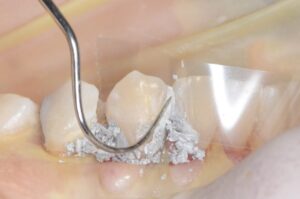

例えば、虫歯がひどく単に充填するだけでは歯の強度を元に戻すのが難しい歯の場合ピンを使います。

下の写真のようにピンを打って支えを作った歯にアマルガムを充填し、そのアマルガムを残したまま、ゴールド修復を行い、歯を被せることによって、強度を取り戻した歯にすることができます。

これらの治療は神経を刺激しない位置にチタン製でできたピンを打ち込まねばならず非常に神経を使う仕事です。